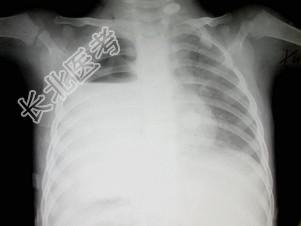

- 单项选择题男,7岁, 外伤后突发呼吸困难伴胸痛,结合图像, 最可能的诊断是 ( )

A、胸腔积液

B、肺大泡

C、气胸

D、液气胸

E、肺脓肿